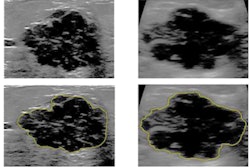

Although previous studies showcase AI's performance in decision support for breast cancer prediction and treatment, they mainly focus on characterizing and classifying soft-tissue lesions and not background parenchymal tissue. However, mammography research also shows there is "significant information" in such background tissue that could help radiologists stratify patient risk and perform lesion-centric risk evaluations, the researchers wrote.

Barinov and colleagues wanted to show that evaluating normal tissue during diagnostic and screening ultrasound exams can assess a patient's risk of having or developing malignant breast lesions. The team looked at 687 cases, of which 197 had examples of malignant lesions. Also out of the total, 39 lesions were deemed to be high risk and 440 were found to be benign.

The AI model (Koios DS Breast, Koios Medical) utilizes a pretrained implementation of ResNet-18 and a combination of features for the network to pool instances of high-risk imaging features. The model also makes use of replication to match ultrasound data with the network's required input dimensionality.